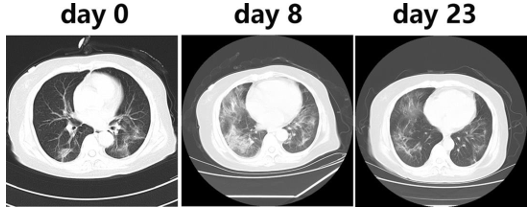

Besides, R. Li et al [8] used the CT imaging for the detection of COVID-19, they reported that the CT scans of all COVID-19 patients showed lung infiltrates and for 86.22%, multiple patchy glassy shadows were observed in the CT images of their both lungs. They also noted that the lesions increased

by the progression of the disease and their scope in size or number expanded (Figure 2). In addition, N. Zhu et al [16] reported that the bilateral fluffy opacities were observed in the CT images of the lungs of a COVID-19 patient after 8 days of onset of symptoms but density, profusion, and the confluence of these bilateral fluffy opacities were increased by the progression of COVID-19 (after 14 days). Also, C. Huang et al. [5] noted that chest CT images of a 40-year-old man with COVID-19 recorded on day 15 after symptom onset showed sub-segmental areas of consolidation and bilateral multiple lobular while the images of a woman (53-year-old) recorded on 8th day after symptom onset showed sub-segmental areas of consolidation and bilateral ground-glass opacity and her CT image recorded after 12 days from symptom onset showed only bilateral ground-glass opacity. Based on the above-mentioned reports, the CT imaging method can be used as a highly accurate method for the clinical diagnosis of the COIVD-19 along with the rRT-PCR.

Figure 2. Chest CT images after 0, 8, and 23 days of onset of COVID-19 (adopted from R. Li et al., 2020 [8]).